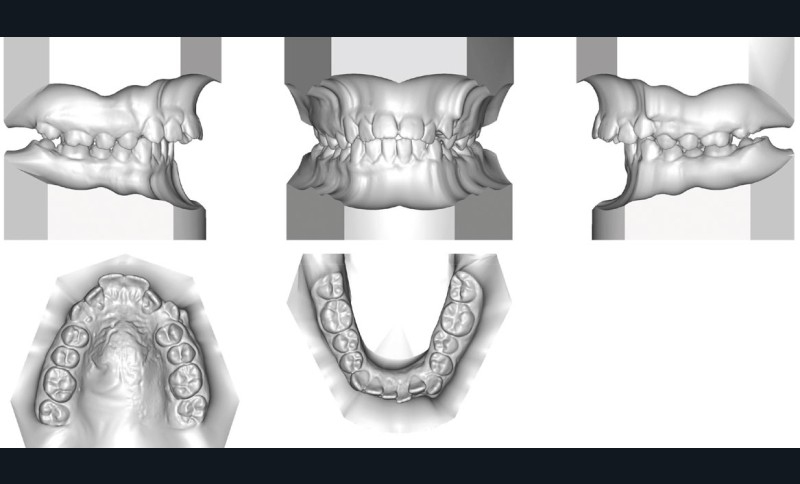

Camille âgée de 12 ans et 7 mois se présente à la consultation adressée par son chirurgien-dentiste.

Son profil convexe s’inscrit dans un contexte de rétrognathie hyperdivergente associée à une proalvéolie et un encombrement maxillo-mandibulaire.